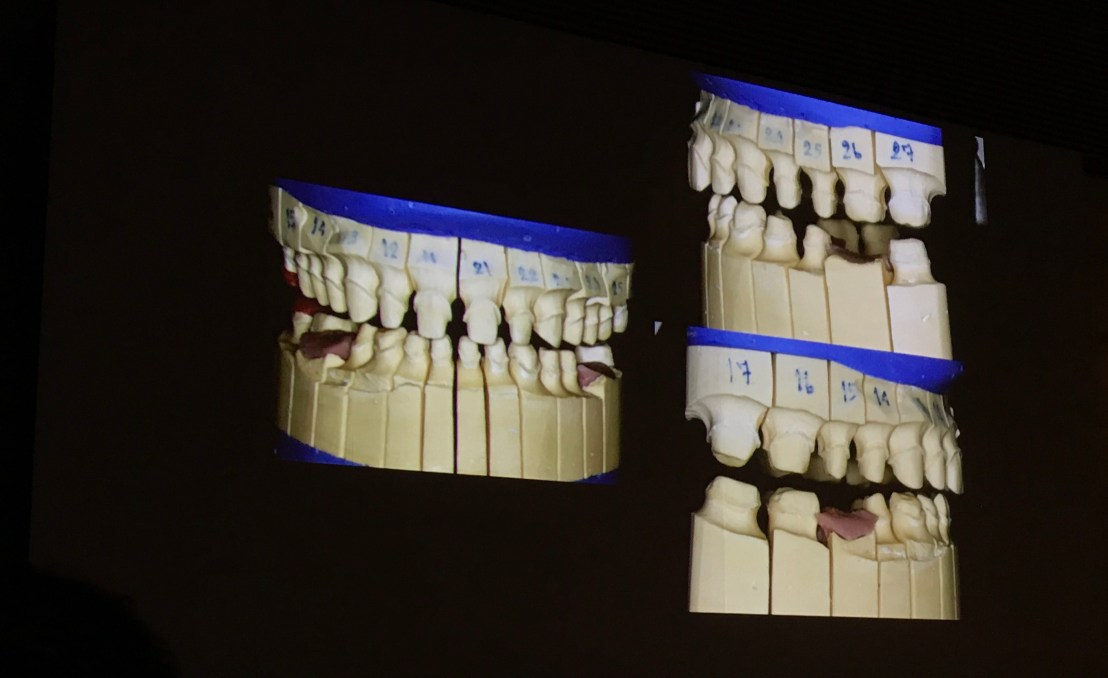

Wax up

ใช้ Pindex system

Transfer facebow เข้า Articulator ใช้ Pindex system

เทียบ Before & After

รูป Before&After

รูป Before& After